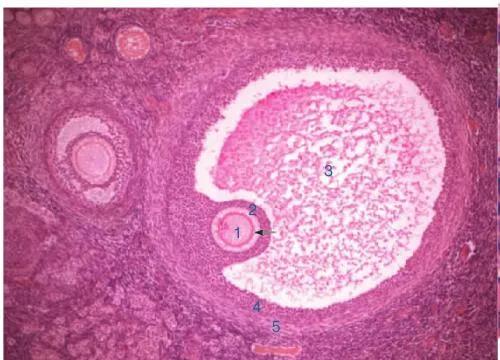

① 透明带缺陷

透明带是包裹在卵子外面的一层柔软的透明组织,我们可以形象的比作“鸡蛋壳”。壳过厚或“过硬”都会影响精子穿透。